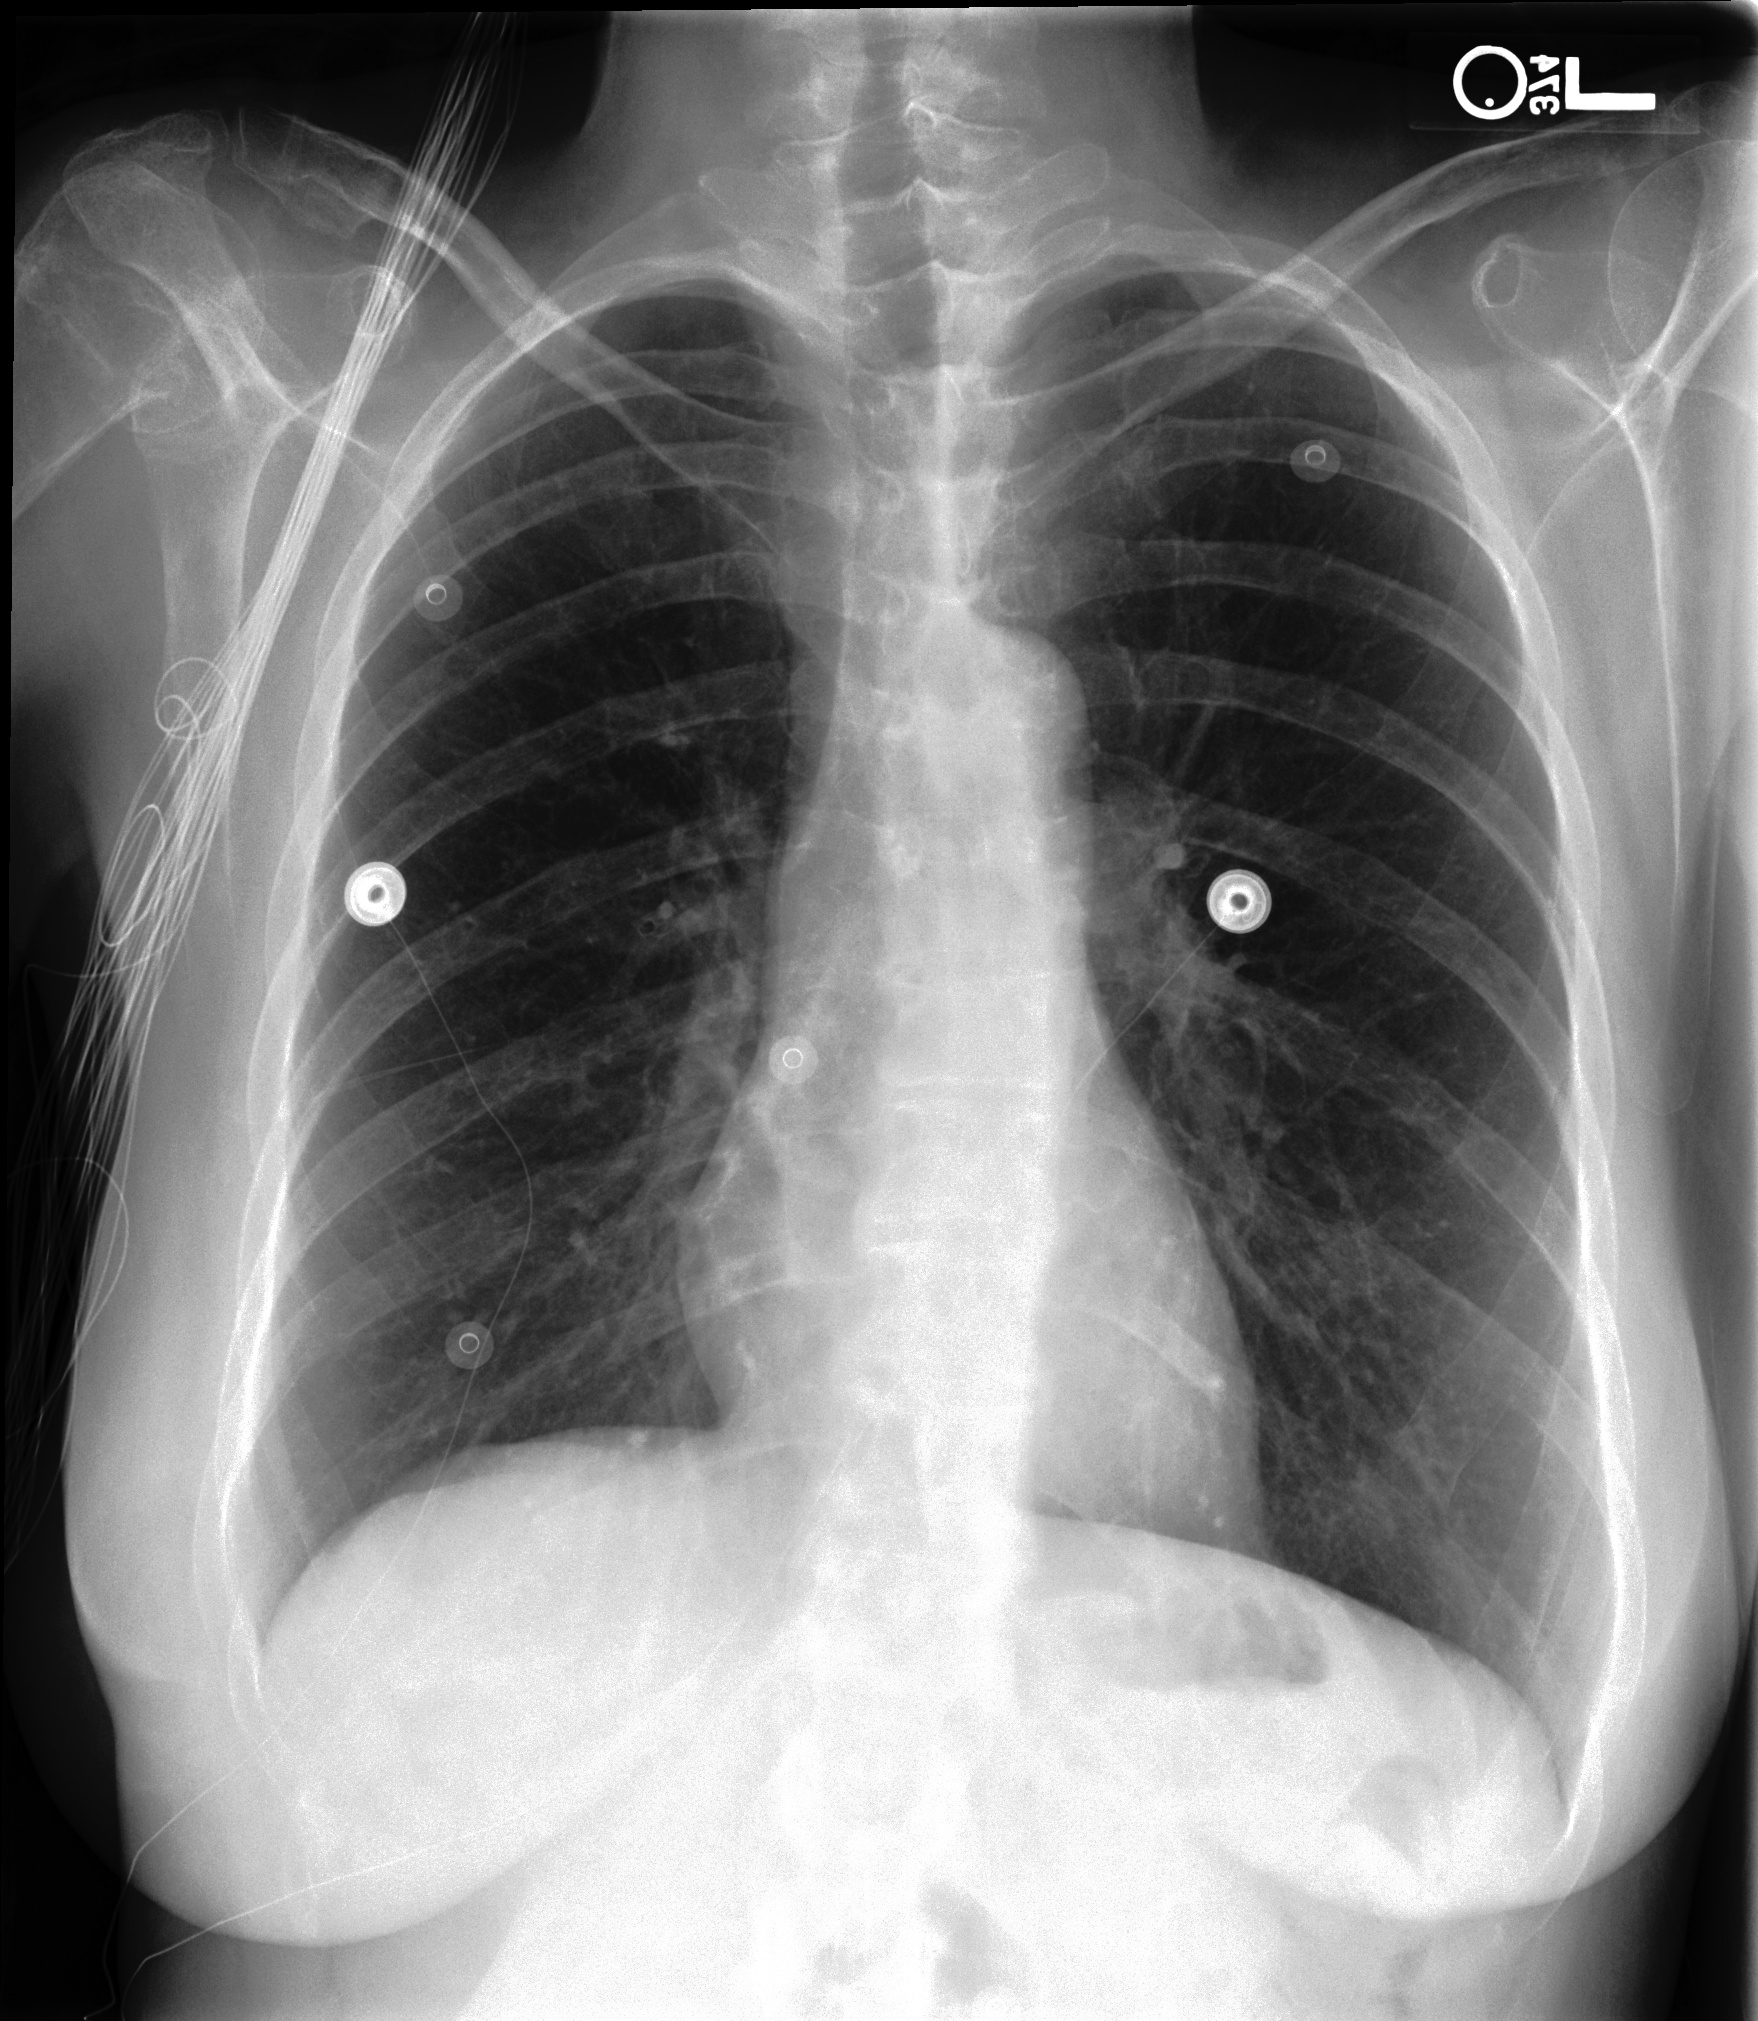

We additionally provided our model performance illustrations in Table 2 containing the original X-Ray images from the MIMIC-CXR dataset, the ground truth expert label and the model prediction (SAT + GPT-3). We manually underlined the similarities and identical diagnoses in texts to guide the eye.

Chest X-Ray Ground Truth Our predictions

[Uncaptioned image] Lungs remain well inflated without evidence of focal airspace consolidation, pleural effusions, pulmonary edema or pneumothorax.Irregularity in the right humeral neck is related to a known healing fracture secondary to recent fall. PA and lateral views of the chest         at 09:55 are submitted. no findings. no pneumonia. no pleural effusion. no edema. there is little change and no evidence of acute cardiopulmonary disease. no pneumonia, vascular congestion, pleural effusion.of incidental note is an azygos fissure, of no clinical significance. this raises possibility of a normal variant.